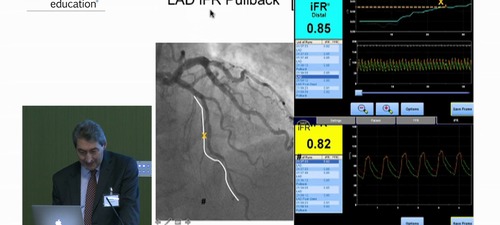

Carlo Di Mario discusses the past, present and future of coronary physiology.

• Clinical trial update (DEFINE-FLAIR, iFR-SwedeHeart, FAME 3)